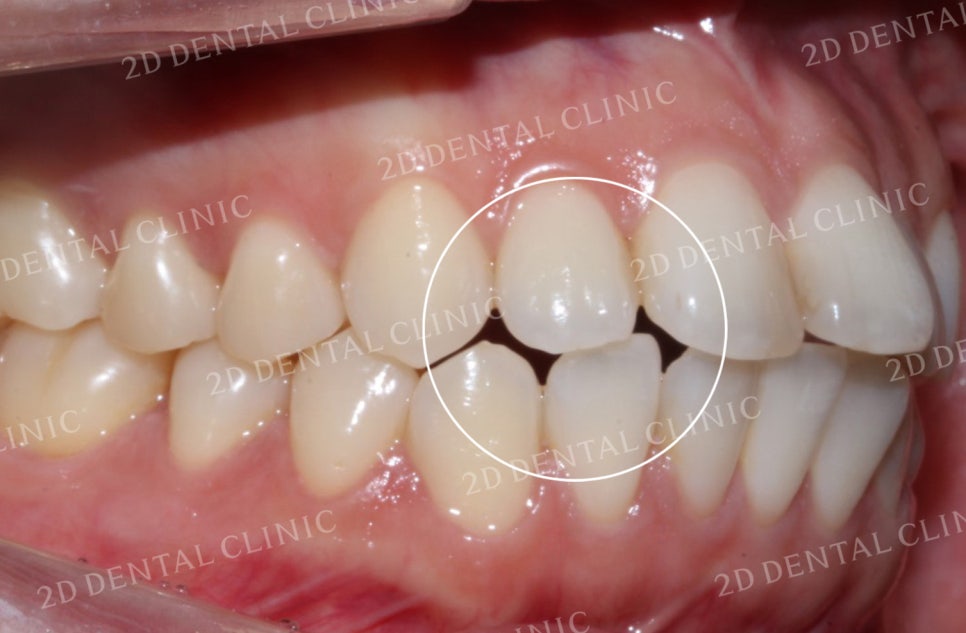

우측 역시 비어있던 공간이

상악의 교정치료 후

잘 덮혀진 모습입니다.